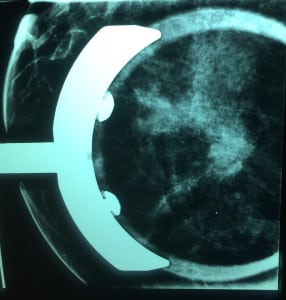

Caso 2.

Mastografía: se ve un nódulo de características sospechosas; deciden hacerle más proyecciones para ver mejor el tumor. Le hacen un ultrasonido y encuentran la sig. imagen:

Las dos proyecciones que siempre se deben hacer en una mamografía son:

- Medio lateral oblicua (se ve músculo pectoral)

- Cráneo caudal